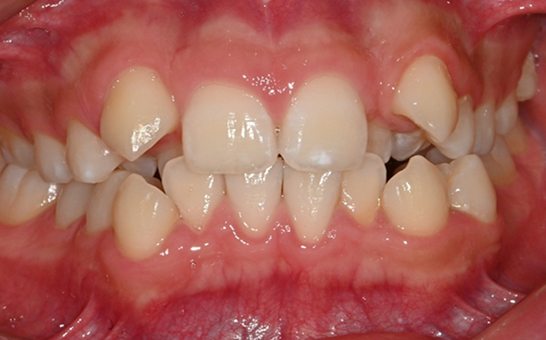

영구치가 나오는 과정에서

공간이 부족한 어린이

앞니의 심한 돌출이나

비대칭으로 인한 기능적

문제가 있는 어린이

턱 성장에 맞춰

치아 교정이 필요한 경우

※ 바른선택치과의원은 의료법을 준수하며 위 케이스는 실제 내원 환자분의 동의하에 공개된 사진과 동일한 환자분께 같은 조건에서 촬영한 사진을 활용했습니다.

개인에 따라 진료 및 치료 방법이 다르게 적용할 수 있으며, 효과와 부작용이 개인마다 다르게 나타날 수 있는 점을 안내해 드리며, 진료 전 전문의료진과 충분한 상담을 권해드립니다.